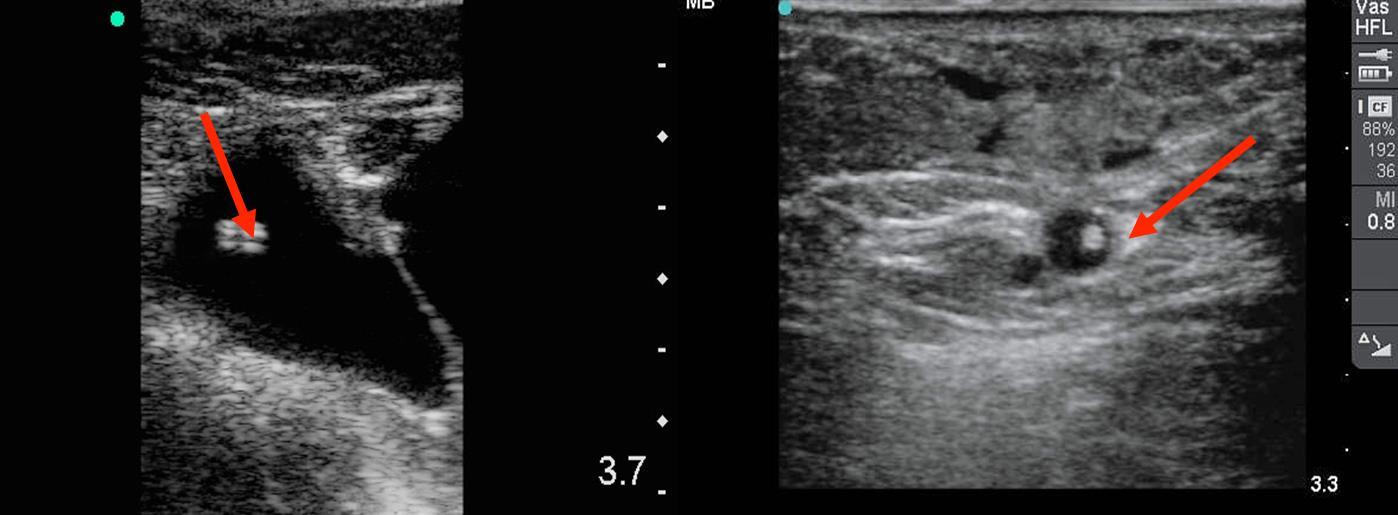

横断断面表示での末梢IV (PIV)カテーテルラインの画像